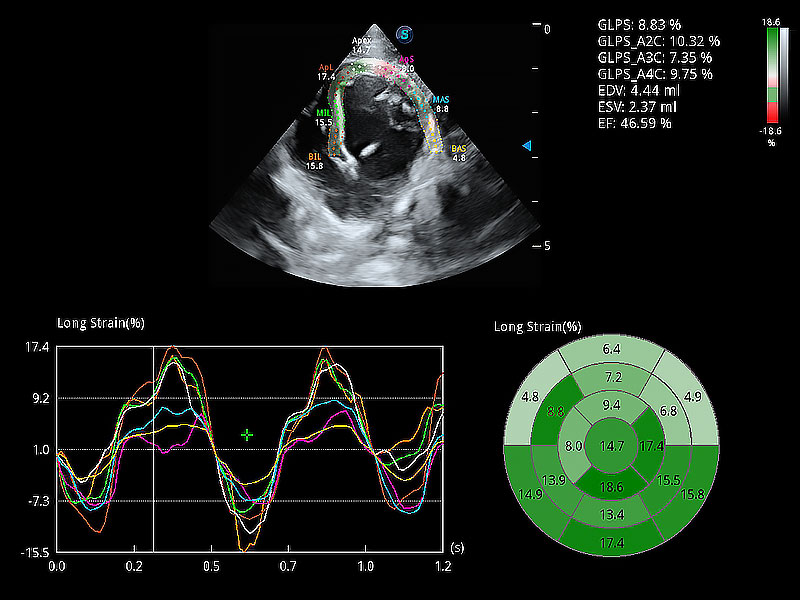

通過(guò)心肌識(shí)別技術(shù)與二維斑點(diǎn)追蹤技術(shù)相結(jié)合,對(duì)心臟的超聲圖像進(jìn)行量化分析。計(jì)算心肌17個(gè)節(jié)段的應(yīng)變、應(yīng)變率、速度、位移等,并通過(guò)牛眼圖的形式進(jìn)行呈現(xiàn)。

能夠基于左心室壁追蹤和辛普森法,自動(dòng)計(jì)算射血分?jǐn)?shù),支持多個(gè)可移動(dòng)點(diǎn)描跡,與手動(dòng)測(cè)量相比,極大節(jié)省了動(dòng)物醫(yī)生的時(shí)間和精力。